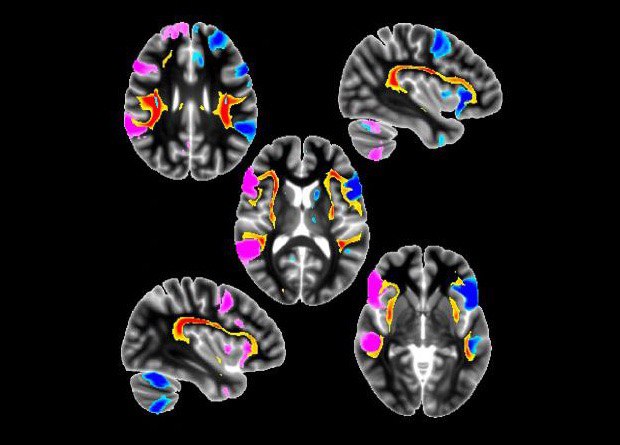

Исследование 400 тысяч человек показало, что у левшей речевые центры из разных полушарий связаны друг с другом лучше, чем у правшей. Есть ли от этого левшам какая-то польза, пока неизвестно. Но ученые нашли еще и генетические особенности — у левшей они меньше связаны с болезнью Паркинсона, но больше с шизофренией

http://short.nplus1.ru/leftright